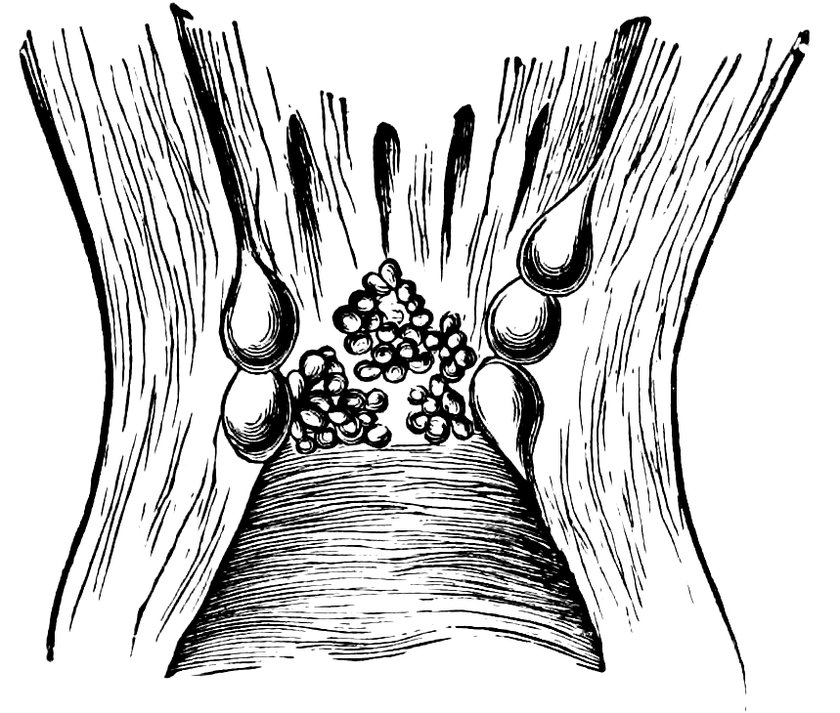

| 95. | Ovula Nabothi in the Portio Vaginalis | 590 |

| 96. | Vesicle (Ovula Nabothi) from the Uterine Mucous Membrane | 591 |

| 97. | Mucous Glands undergoing Cystic Degeneration | 592 |